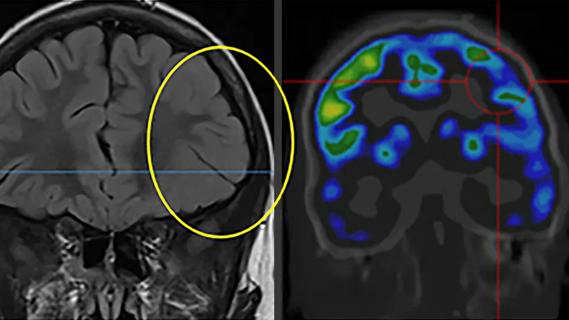

two brain scans side by side with a yellow circle on the left scan

March 13, 2026/Neurosciences/Epilepsy

SEEG Linked With More Complete Resection and Greater Seizure Freedom in MOGHE Subtype of Epilepsy

Insights from one of the first studies of invasive monitoring in the rare form of focal cortical dysplasia